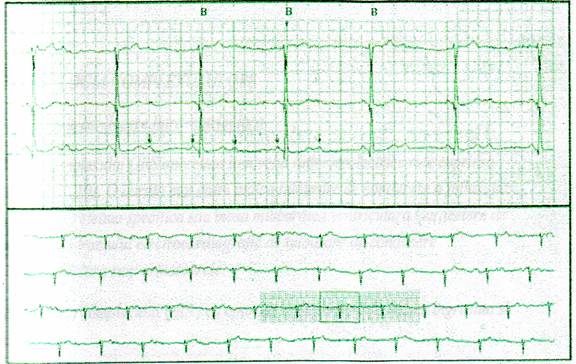

a) Electrocardiografia

Electrografia (ECG) este o inregistrare grafica a activitatii cardiace electrice captata prin electrozi plasati la suprafata corpului in anumite pozitii. Inregistrarile clinice sunt facute pe hartie care are un carionaj ce permite masurarea rapida a intervalelor de timp si voltaj. Liniile verticale de timp sunt la distanta de 1mm, fiecare a cincea linie fiind ingrosata. La viteza obisnuita de inregistrare de 25 mm/s, 1mm=0,04 s, iar intre doua linii groase 0,20s. Liniile orizontale permit calibrarea oltajului, 1mm=0,1mV, iar 10mm=1mV.

Standardizarea ECG

Unda P reflecta depolarizarea atriala, initiind de fapt ciclul cardiac.

Depolarizarea venriculara este reprezentata de complexul QRS. Unda Q este prima unda negativa, atunci cand la revenirea la linia izoelectrica nu este urmata de o unda pozitiva, comlexul este numit QS. Daca dupa unda R apare a doua unda pozitiva, aceasta este notata R “ansamblul fiind considerat RR”. Unda reprezinta repolarizarea musculaturii ventriculare urmata uneori de unda U, cu mecanism inca necunoscut. Repolarizarea musculaturii atriale este reprezentata de omica unda numita Ta, dar aceasta este dificil de identificat depoarece ea se desfasoara pe parcursul intervalului PR si a complexului QRS. Intervalul intre sfarsitul complexului QRS si inceputul undei T este numit segmentul ST, el reprezentand perioada de timp intre depolarizarea ventriculara si repolarizarea rapida a lor. Intervalul dintre debutul depolarizarii atriale (P) si debutul depolarizarii ventriculare (Q sau R) orienteaza asupra timpului de conducere atrio-ventricular, valori normale situandu-se intre 0,12-0,21 s. Durata complexului QRS, normala intre 0,04-0,10 s reprezentand timpul necesar pentru depolarizarea musculaturii ventriculare. O aproximare a perioadei refractere a ventriculilor poate fi obtinuta prin masurarea intervalului QT, de la debutul QRS pan la sfarsitul undei T.